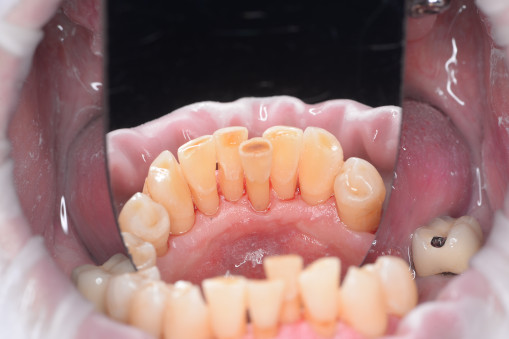

А прежде, чем вы посмотрите фотографии «до» и «после» лечения слизистой оболочки полости рта, проведенных в нашей клинике, хочу поблагодарить большое количество наших пациентов, которые поверили, прониклись нашей концепцией, и мы вместе, именно вместе победили болезни десны, гингивит и пародонтит!

До/после лечения